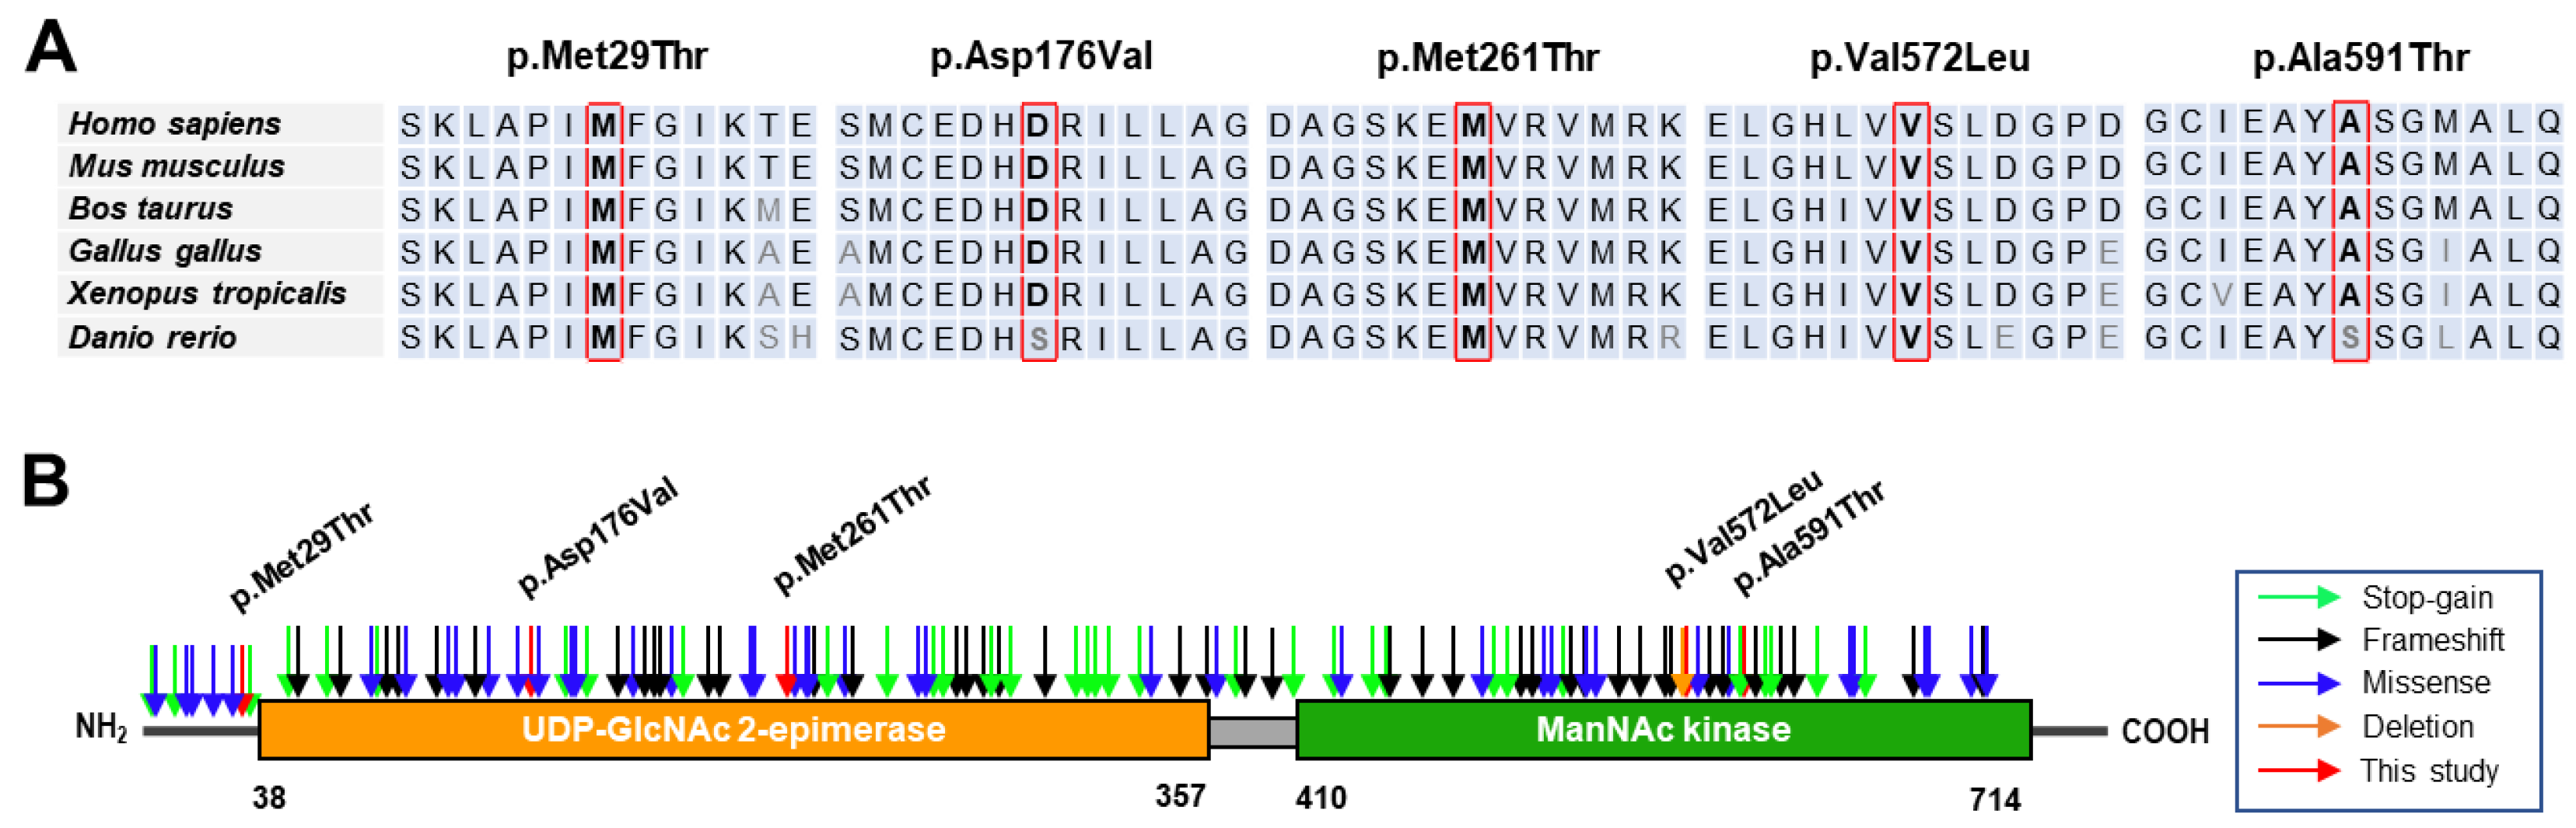

3.2. Conservation Analysis and In Silico Prediction of the Mutation Effects

| Variant 1 | Domain | dbSNP | GERP | In silico Prediction 2 | ||||

|---|---|---|---|---|---|---|---|---|

| Nucleotide | Amino Acid | PP2 | MutT | MUp | REVEL | |||

| c.86T>C | p.Met29Thr | Epimerase | UR | 4.83 | 0.983 * | 1.00 * | −1.00 * | 0.93 * |

| c.527A>T | p.Asp176Val | Epimerase | rs139425890 | 5.67 | 0.108 | 0.99 * | −0.11 * | 0.80 * |

| c.782T>C | p.Met261Thr | Epimerase | UR | 5.77 | 0.996 * | 0.94 * | −1.00 * | 0.84 * |

| c.1714G>C | p.Val572Leu | Kinase | rs121908632 | 5.75 | 0.968 * | 0.96 * | −0.36 * | 0.83 * |

| c.1771G>A | p.Ala591Thr | Kinase | rs752286512 | 5.75 | 0.957 * | 0.94 * | −0.38 * | 0.77 * |